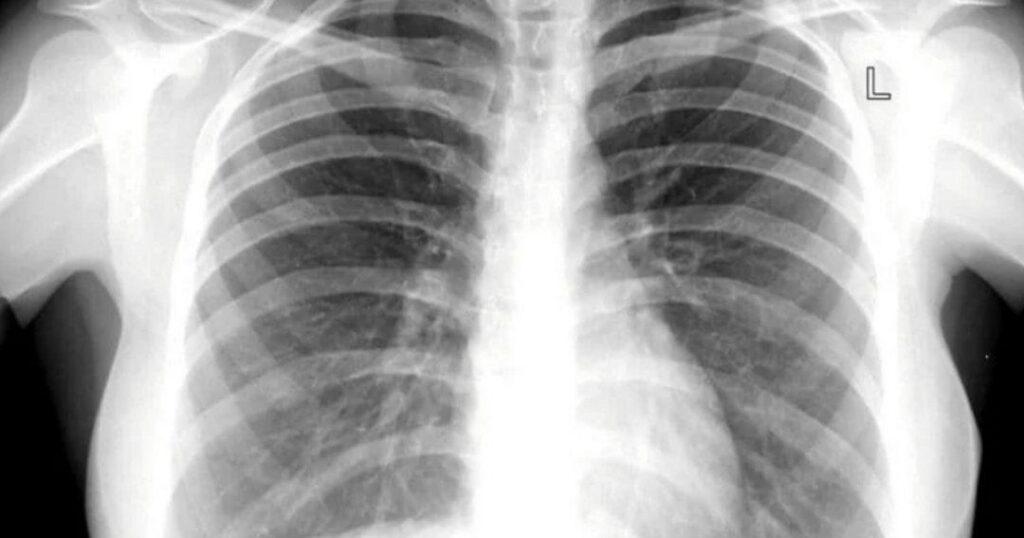

NEWS | Tubercolosi, aumentano i casi: il Lazio tra le regioni più colpite

Il Ministero della Salute ha pubblicato il report epidemiologico sulla tubercolosi ed è emerso che i casi stanno aumentando, la situazione non è allarmante ma da tenere sotto controllo. L’Italia resta è un paese a bassa endemia...> TUBERCOLOSI <